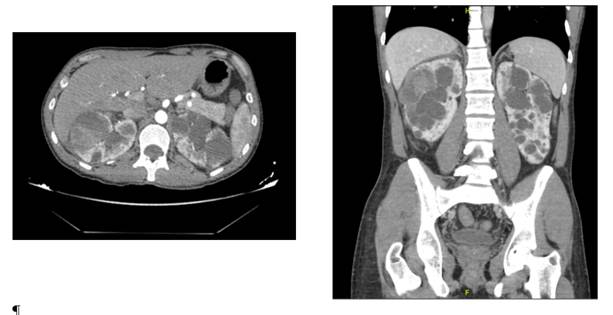

Case 3

A 42-years-old male with no medical history, presented to the ER of another center with abdominal pain after falling from an e-scooter at 30km/h while riding it under alcohol influence, 3 days later the patient presented to our ER for persistence of pain. Physical examen showed pain with the abdominal palpation but without alarming findings. A CT scan was performed noticing a left kidney inferior pole hypoperfusion, a spleen laceration, and a left lung contusion (Figure 5 & 6). Classified as a AAST grade IV, the patient was hospitalized for close vigilance, kept stable during hospital admission with normal GFR and hemoglobin therefore receiving a conservative management and was sent home with no complications. The follow up CT showed resolution of the lesions.